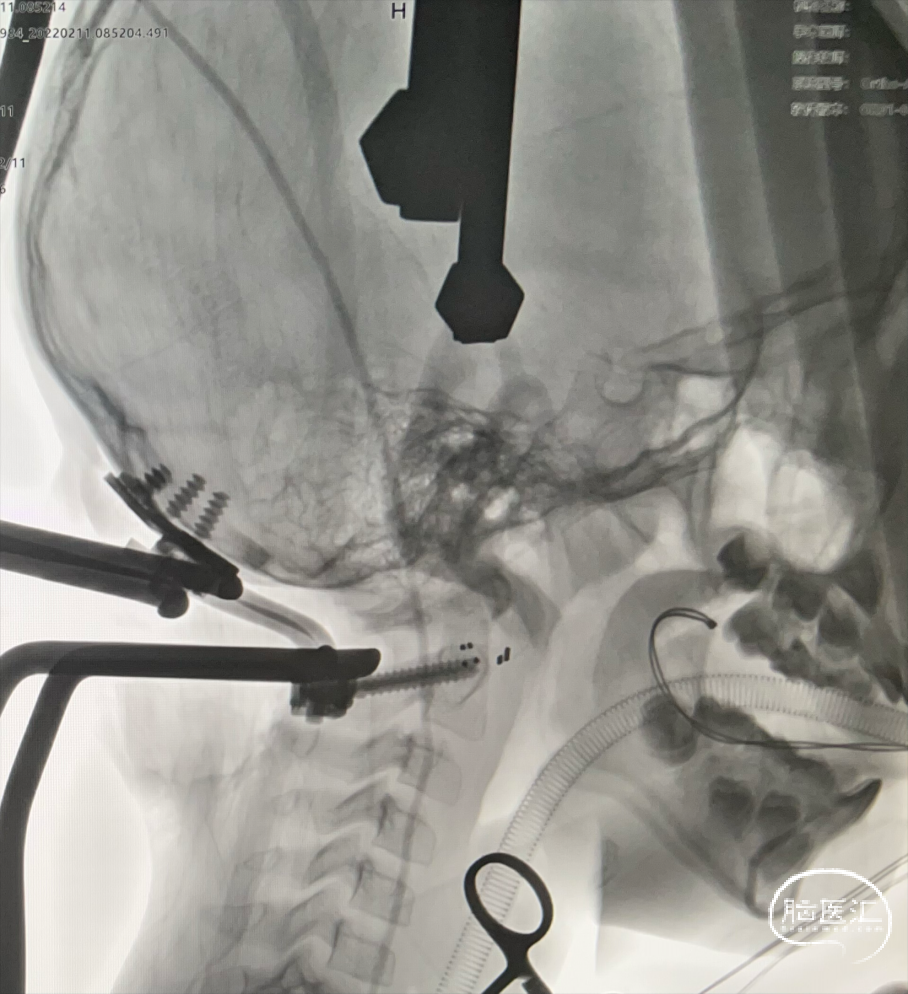

南⽅医科⼤学附属南⽅医院神经外科脊髓与脊柱亚专业组在漆松涛主任及陆云涛教授的带领下先后针对不同类型颅底凹陷症300余例。总结积累了不同群体及不同类型颅底凹陷症的诊治经验,获得业界认同的同时也在国际级对应领域获得同⾏赞许。